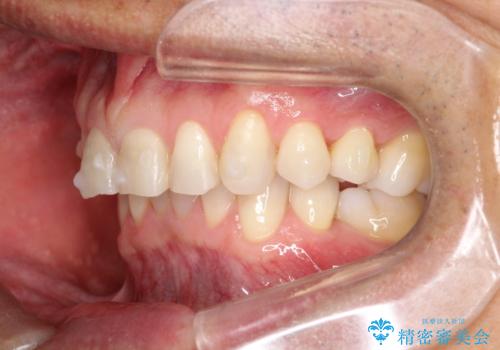

上の前歯の隙間とがたつきをインビザラインできれいな歯並びへ

- 以前矯正治療を他院にて行っており、最近上顎の隙間とガタガタが気になるとのことで来院されました。

上顎のみインビザラインにて矯正治療を行うこととなりました。

使用時間を守っていただけたので、比較的スムーズに矯正を終了することができました。